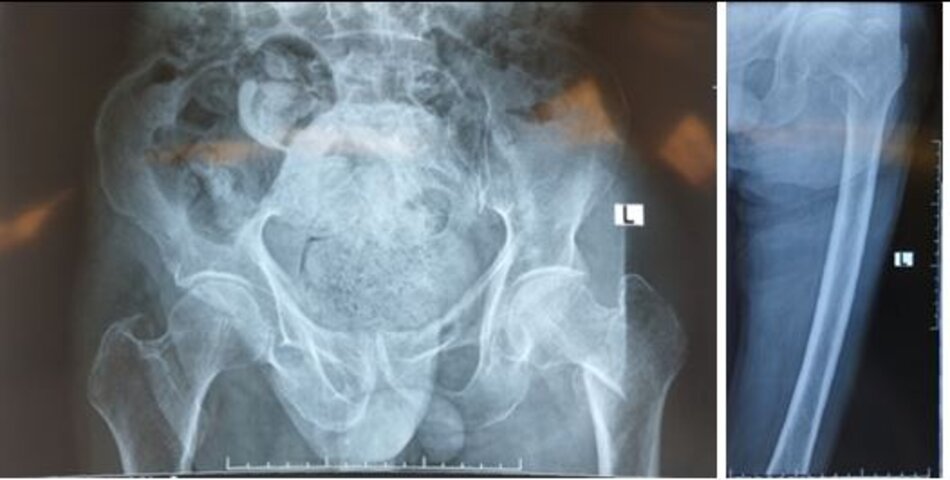

Xquang trước mổHình ảnh hoại tử chỏm xương đùi trái

Xquang trước mổ. Hình ảnh hoại tử chỏm xương đùi trái

Xquang trước mổHình ảnh dính hoàn toàn khớp háng trái

BN nam 45 tuổi, viêm dính khớp háng 2 bên gây ra tình trạng khớp háng cứng chắc, không thể gấp duỗi

Xquang trước mổ. Hình ảnh dính hoàn toàn khớp háng trái. BN nam 45 tuổi, viêm dính khớp háng 2 bên gây ra tình trạng khớp háng cứng chắc, không thể gấp duỗi